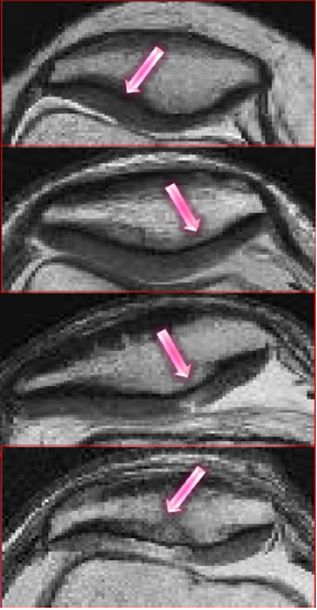

距腓前韧带撕裂

五、三角骨综合症

三角骨是距骨后端二次化中心,由软骨桥相连接。

病因:距骨三角骨急性骨折或慢性应力性骨折,胫骨后部或附近肌腱韧带反复撞击、压迫三角骨,引起踝关节囊后部级相邻的韧带和拇长屈肌腱的炎症。

MRI显示三角骨内骨髓水肿,邻近关节囊积液,软组织水肿级炎症,拇长屈肌腱水肿、腱鞘积液。